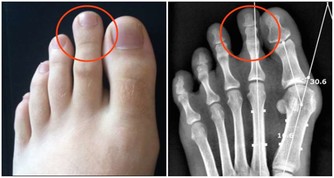

當體液中尿酸濃度超過此值時,將因過剩而在組織中沉積,這種尿酸鹽的結晶沉積在關節滑膜、關節骨、軟骨而導致痛風性關節炎,沉積在皮下則形成痛風石。中西醫均會要求痛風患者不可以攝取高普林食物,然而這些食物可以說是最起碼的美食,要痛風病患完全不吃這些食物,說真的,這種治療的犧牲代價還不小呢!

嘉眾草師表示,許多人耽心椰子會不會太涼?其實這是多慮了,因為患有痛風的人,本身體質會偏燥,高普林會不斷累積,椰子水正好可以清洗積存的痛風石,這是西藥秋水仙很難做到的。痛風的確是一種令病人非常痛苦的一種病症,當它發作的時候,可以說是「痛不欲生」,這種毛病還真會整人,它發作時間通常是選擇在夜深人靜的時刻。